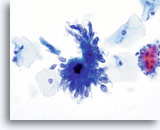

Adenocarcinoma in situ

Endocervical cells presenting in a pseudo-rosette formation and exhibiting “feathering” and nuclear elongation due to crowding. Biopsy – AIS – 60x